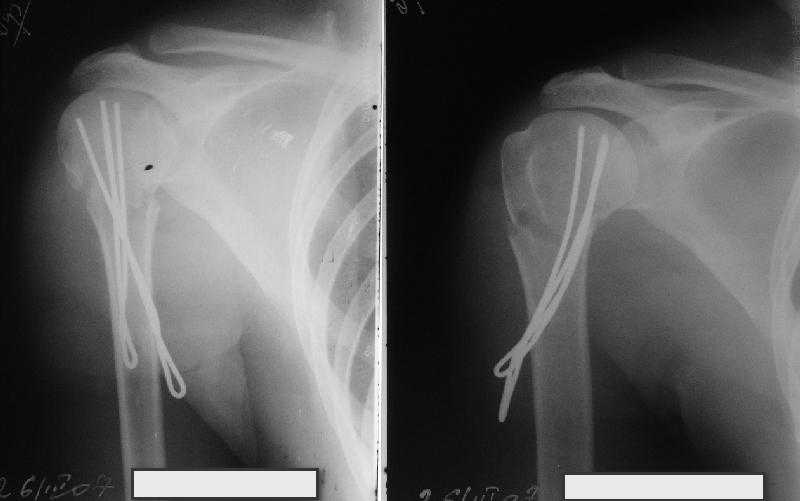

Неплохой бюджетный и косметический вариант, хотя в руках автора это это очень просто, а у нас приходилось "посветиться ", репозицию проводили

короткими 2 мм спицами -джойстиками,их же использовали для временной фиксации (а в некоторых случаях и для окончательной), варинат фиксация

TENами.

Сделали напряженными спицами по методике А.Ф.Лазарева со товарищи Репозиция сделана спицевым дистрактором, проксимальная спица была проведена в полскости деформации перпендикулярно оси наклонившейся головки. Получилось все довольно легко. Спицы малость покороче можно было сделать, ну да удалять потом легче будет.